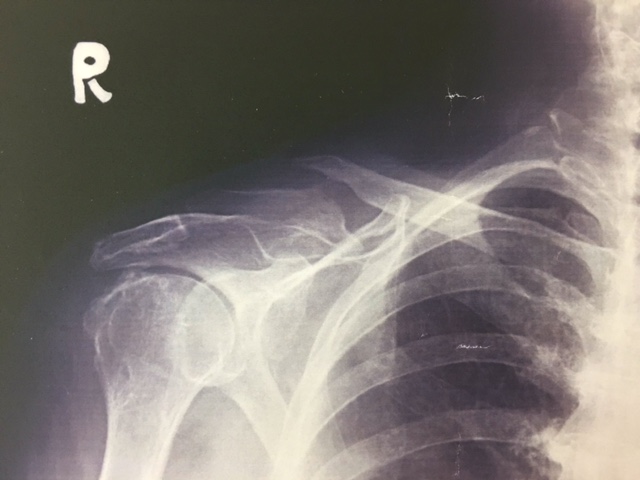

さて、今回は『鎖骨骨折』について、紹介させていただきます。

それは鎖骨の形状にあります。鎖骨はS状の骨でありその曲がっているところに力が集中してしまうからです。そのため骨の丈夫な方でも骨折してしまうのです。

一般的には、大きな衝撃により起こるといわれ、スポーツや運動中の転倒で起きやすいです。また、骨粗しょう症などで骨がもろくなってしまっている場合には、軽い転倒でも骨折してしまいます。

鎖骨骨折はずれを生じることがほとんどであるため、適切な処置を行わなくてはいけません。自己判断でそのままにしていると、手にシビレが出たり、手が挙がらなかったりと後遺症が残ってしまいます。